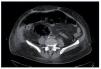

Ante la sospecha de sepsis de origen urinario se inicia antibioterapia con ceftriaxona, hidratación intensiva y corrección de la glucemia y de la acidosis. Sin embargo, la evolución de la paciente es tórpida, y persisten cifras de presión arterial en el límite inferior de la normalidad, mal estado general, desorientación y oligoanuria mantenida. De esta manera, a las 24 h del ingreso se realiza ecografía abdominal urgente, en la que no se logra visualizar el injerto renal. Ante este hallazgo, asociando empeoramiento progresivo de la función renal y progresión a la anuria, con requerimiento de hemodiálisis, se realiza tomografía computarizada (TC) abdominal sin contraste. En ella se objetiva destrucción del parénquima del injerto renal que se manifiesta por la presencia de acúmulos moteados y lineales de gas, tanto a nivel intrarrenal como en el espacio perirrenal, sin condensaciones líquidas (fig. 1). Los hallazgos son compatibles con PE de injerto con destrucción y distorsión prácticamente completa de este (tipo I de la clasificación de Wang). A las 48 h del ingreso se obtiene el resultado de los aislamientos microbiológicos: en el urocultivo y en el hemocultivo se aisla E. coli resistente a amoxicilina, cefalotina y ácido nalidíxico, sensible al resto de antibióticos testados.

Figura 1. TC abdominal sin contraste, observándose la destrucción del parénquima del injerto renal con acúmulos de gas intrarrenal y en el espacio perirrenal.